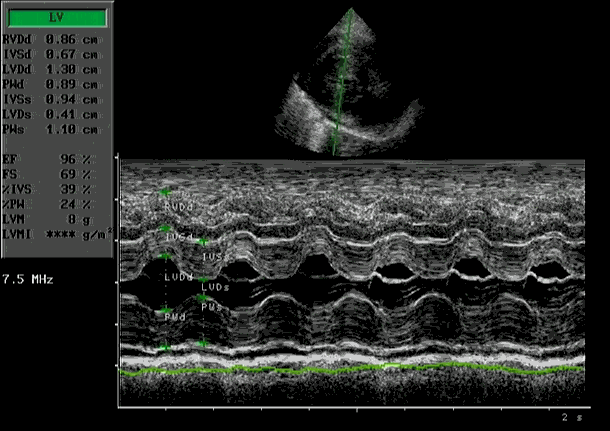

De diagnose kan alleen gesteld worden met een echocardiogram gecombineerd met kleuren Doppler.

Dit onderzoek zegt niet alleen iets over de beweging en grootte van de diverse hart-structuren, maar ook iets over het functioneren van het hart. De wanden van het normale hart zijn normaal 0,55-06 cm. Bij HCM is dit vaak meer dan 0,9 cm.

| Verdikte wanden linker kamer | Flowmeting met Doppler |

| M-mode met abnormale mitraalklepbeweging | (foto: Putcuyps) |

Verdikking vrije linker kamerwand

| SAM HCM Systolic Anterior Motion is typisch voor HCM. Hierbij beweegt de mitraalklep naar voren tijdens het samentrekken van de linker kamer |